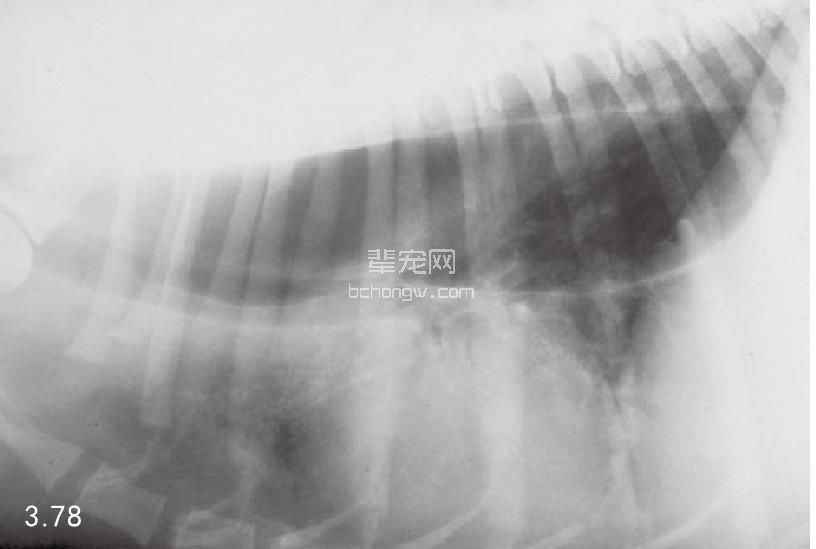

诊断 通过病史和胸腔常规X线片可以诊断 (图3.77~图3.80),但如果需要确定特殊的病 因,则需要进行额外的试验(表3.7)。如果不能 确诊可以做食管X线片和食管镜试验,但通常没有 这个必要(图3.81和图3.82)。德国牧羊犬、大丹 犬、爱尔兰赛特犬、小型雪纳瑞犬和硬毛 易患 先天性巨食管症。犬胃扩张-扭转综合征时,也 可能暂时性继发巨食管症。

图3.77 16周龄德国牧羊犬具有“玩耍时发生呕吐”史,胸腔X线检查发现为巨食管症。

图3.78和图3.79 在图3.77中所述幼犬的食道造影X线片可见食管的巨大扩张。